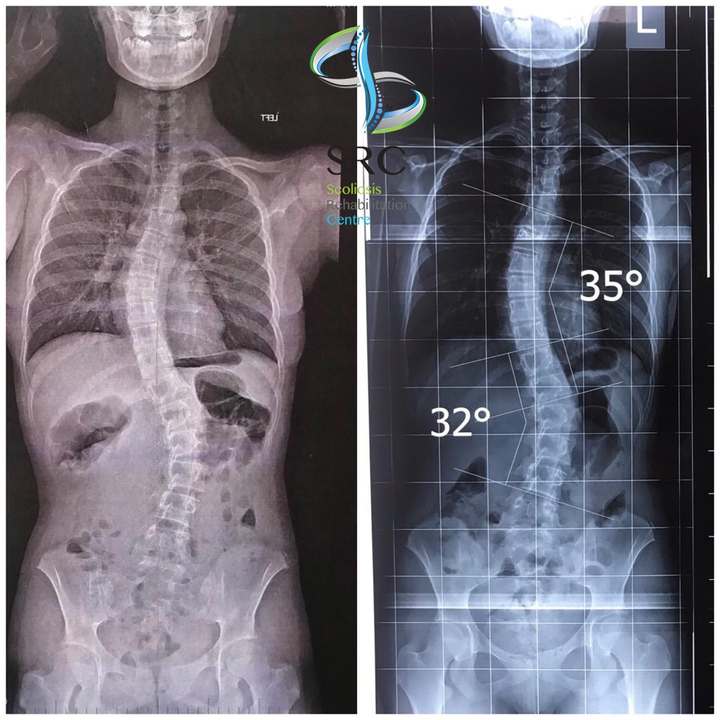

- Radiological changes - improvement can be expressed numerically on an Xray image, in which we measure the difference in Cobb angle (angle of curvature), vertebral rotation, iliac bone level, the distance between the farthest vertebra of the scoliotic curve from the central line as well as the improvement of the balance itself. In cases where scoliosis is very progressive, stopping further bending of the spinal column and controlling the scoliotic curve is considered a positive result.